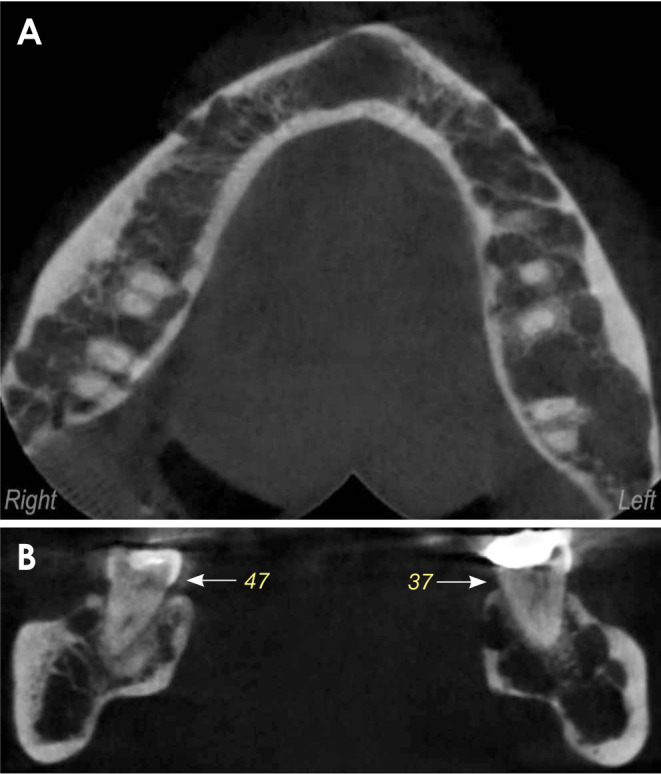

非分泌性多发性骨髓瘤(NSMM)是一种罕见的浆细胞癌症,其特点是血液或尿液中检测不到单克隆M蛋白。一名 57 岁的妇女出现下颌骨疼痛,但无口内肿胀。影像学检查发现她的下颌骨有多处溶骨性病变,左下颌第二磨牙的牙根明显吸收。活检结果显示,非典型浆细胞的抗卡帕抗体、CD138抗体、MUM1抗体和CD79a抗体呈阳性,但抗蓝斑抗体和CD20抗体呈阴性。这些结果表明是恶性浆细胞肿瘤。游离轻链检测、血清或尿蛋白电泳均未发现异常,因此诊断为非小细胞肺癌。患者开始接受化疗和双膦酸盐治疗,治疗后病情得到缓解。本病例强调了牙科医生在早期发现和预防NSMM并发症方面的关键作用,因为这种疾病最初可能出现在口腔中。

Non-secretory multiple myeloma (NSMM) is a rare cancer of plasma cells characterized by the absence of detectable monoclonal M protein in the blood or urine. A 57-year-old woman presented with mandibular pain but without intraoral swelling. Imaging studies revealed multiple osteolytic lesions in her mandible and pronounced root resorption of the left mandibular second molar. Biopsy results showed atypical plasmacytoid cells positive for anti-kappa, CD138, MUM1, and CD79a antibodies, but negative for anti-lambda and CD20. These results were indicative of a malignant plasma cell neoplasm. No abnormalities were revealed by free light chain assay or by serum or urine protein electrophoresis, leading to a diagnosis of NSMM. The patient began chemotherapy in conjunction with bisphosphonate therapy and achieved remission following treatment. This case underscores the critical role of dentists in the early detection and prevention of NSMM complications, as the disease can initially present in the oral cavity.